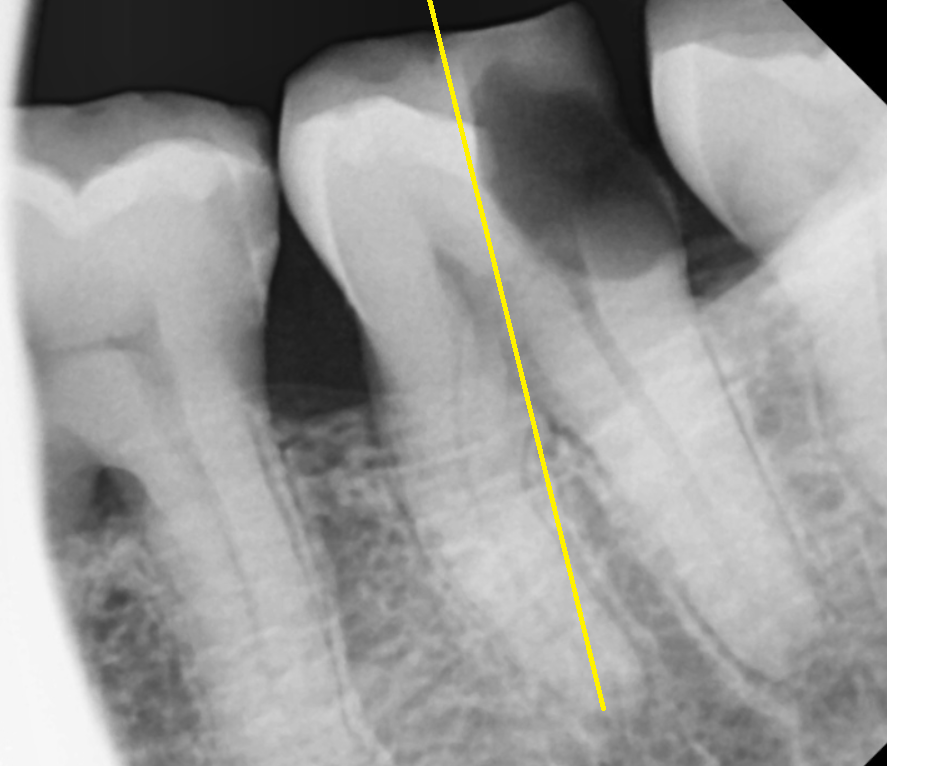

x-ray를 한장 더 찍어 보았습니다.

230918

절반을 비교해보았을 때

왼쪽과 오른쪽의 차이

느껴지시나요?

충치가 없는 부위는 하얗게 표시되지만

이가 썩게되면

충치 벌레가 내 치아 속을 다 파먹습니다.

내부가 텅~~비기 때문에

까맣게 보여지게 되는데요.

손상된 치아 부분

이제 눈에 확! 들어오시죠~?

충치가 절반 이상 먹었네요.

뿌리쪽까지 깊게 썩었는데요.